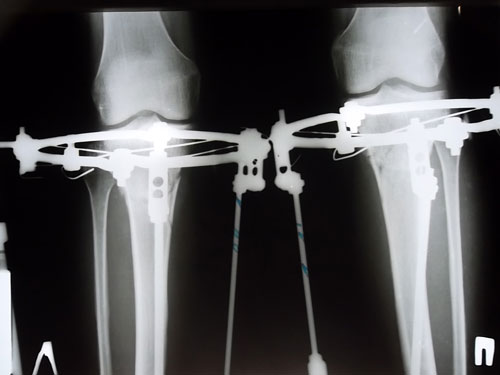

90 дней с момента операции.

Рентгеновские снимки.

Сращение отличное, Ваша подвижность и подготовка к ремонту, пошла Вам на пользу! :lol: